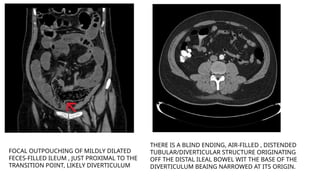

FOCAL OUTPOUCHING OF MILDLY DILATED

FECES-FILLED ILEUM , JUST PROXIMAL TO THE

TRANSITION POINT, LIKELY DIVERTICULUM

THERE IS A BLIND ENDING, AIR-FILLED , DISTENDED

TUBULAR/DIVERTICULAR STRUCTURE ORIGINATING

OFF THE DISTAL ILEAL BOWEL WIT THE BASE OF THE

DIVERTICULUM BEAING NARROWED AT ITS ORIGIN.